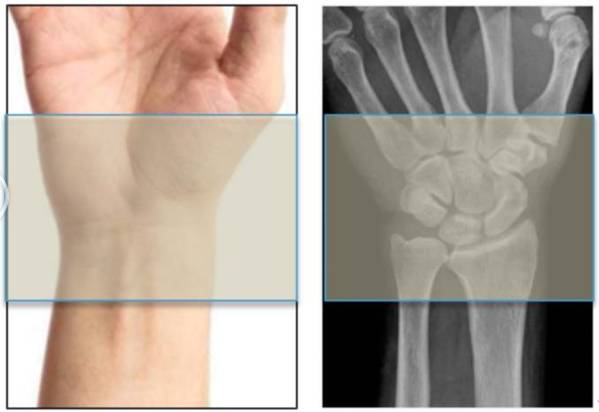

张文龙手外科学习笔记